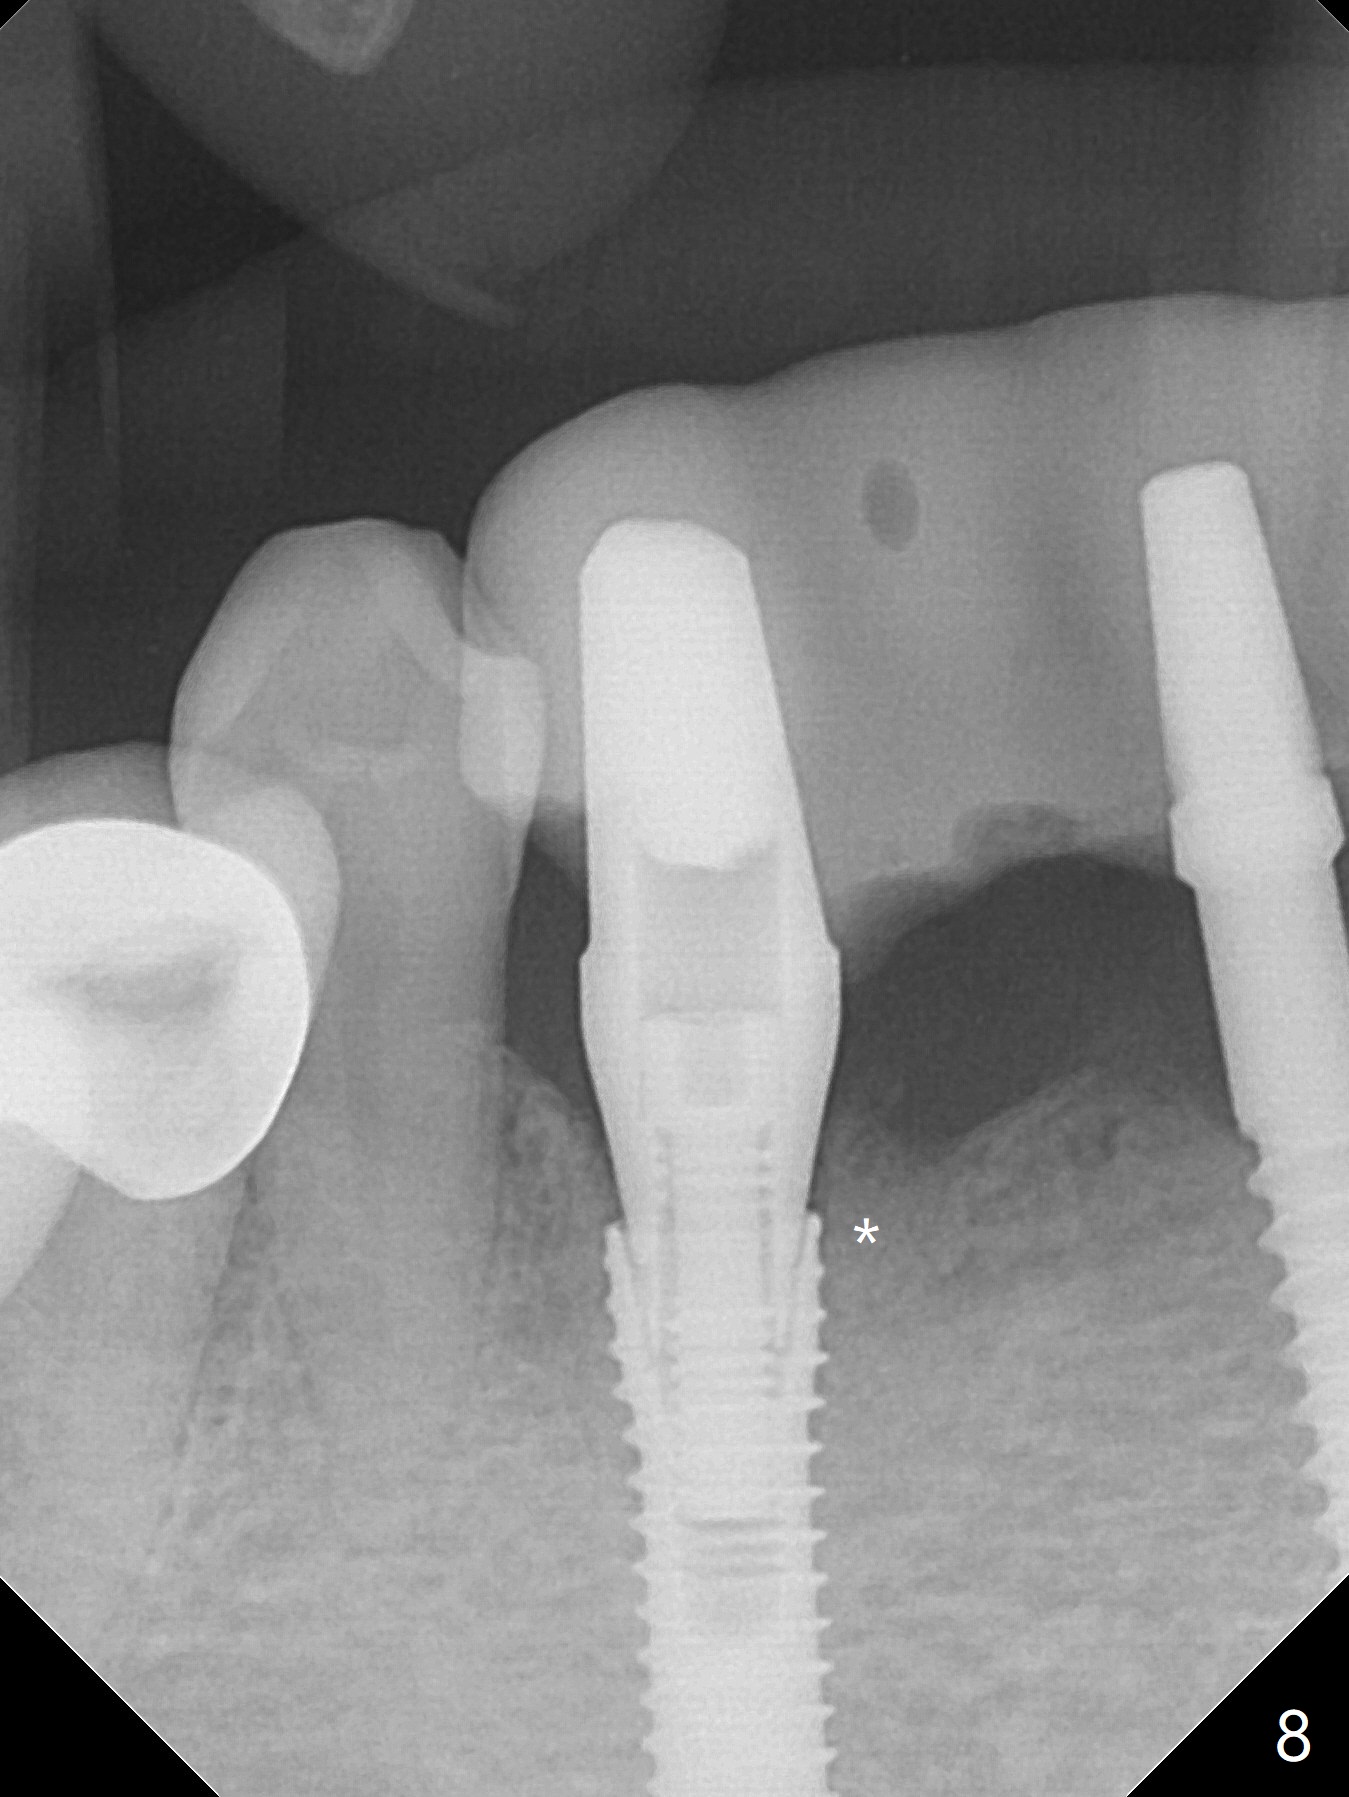

The mesial defect at #27 appears to have been repaired 8 months postop (Fig.8,9 *); there is no bone loss at 1-piece implant sites. The gingival recession seems to remain the same before and after removal of the provisional FPD (Fig.10,11). The bulging abutment at the cervix is less prominent when a straight abutment is used and prepared (Fig.12, 4.5x5.5(5) mm). There is no bone loss at #23, 25 and 27 sites 2.5 years post cementation (Fig.12-15), although the trajectory of the implants could be improved by using surgical guide (Fig.16-18).